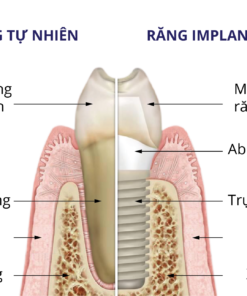

PHỤC HÌNH CỐ ĐỊNH TRÊN 4-6 TRỤ IMPLANT